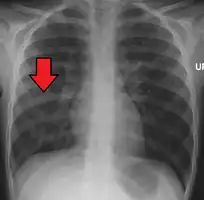

Chest X-ray of a pneumonia caused by influenza and Haemophilus influenzae, with patchy consolidations, mainly in the right upper lobe (arrow)

Pneumonia is usually caused by infection with viruses or bacteria and less commonly by other microorganisms, certain medications or conditions such as autoimmune diseases.[3][4] Risk factors include cystic fibrosis, chronic obstructive pulmonary disease (COPD), sickle cell disease, asthma, diabetes, heart failure, a history of smoking, a poor ability to cough (such as following a stroke), and a weak immune system.[5][7] Diagnosis is often based on symptoms and physical examination.[8] Chest X-rays, blood tests, and culture of the sputum may help confirm the diagnosis.[8] The disease may be classified by where it was acquired, such as community- or hospital-acquired or healthcare-associated pneumonia.[15]

A chest radiograph is frequently used in diagnosis.[20] In people with mild disease, imaging is needed only in those with potential complications, those not having improved with treatment, or those in which the cause is uncertain.[20][60] If a person is sufficiently sick to require hospitalization, a chest radiograph is recommended.[60] Findings do not always match the severity of disease and do not reliably separate between bacterial infection and viral infection.[20]

X-ray presentations of pneumonia may be classified as lobar pneumonia, bronchopneumonia, lobular pneumonia, and interstitial pneumonia.[66] Bacterial, community-acquired pneumonia classically show lung consolidation of one lung segmental lobe, which is known as lobar pneumonia.[34] However, findings may vary, and other patterns are common in other types of pneumonia.[34] Aspiration pneumonia may present with bilateral opacities primarily in the bases of the lungs and on the right side.[34] Radiographs of viral pneumonia may appear normal, appear hyper-inflated, have bilateral patchy areas, or present similar to bacterial pneumonia with lobar consolidation.[34] Radiologic findings may not be present in the early stages of the disease, especially in the presence of dehydration, or may be difficult to interpret in the obese or those with a history of lung disease.[21] Complications such as pleural effusion may also be found on chest radiographs. Laterolateral chest radiograph can increase the diagnostic accuracy of lung consolidation and pleural effusion.[33]